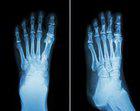

(图:申先生治疗后的脚部X光)

第一个疗程治疗后,申先生的双足关节刺痛感减轻,晨起僵硬有所缓解,夜间发作次数也减少了。

第二个疗程治疗后,申先生的双足第一跖趾关节痛风石溶解不少,按压无疼痛,夜间不再发作。郑州痛风风湿病医院又为其安排了一个疗程的辅助治疗,采用无针介入术,控制关节炎症发展,阻止骨质继续受损,修复受损软骨组织改善活动能力的治疗效果与 巩固目的。

第三个疗程治疗后,申先生的双足第一跖趾关节痛风石已全部溶解,关节活动恢复正常状态。复查也显示各项指标均一切正常,已达临床 标准。离院前,郑州痛风风湿病医院嘱咐申先生,回去后要合理饮食,多饮水,多食水果蔬菜,适当锻炼身体,不可熬夜。